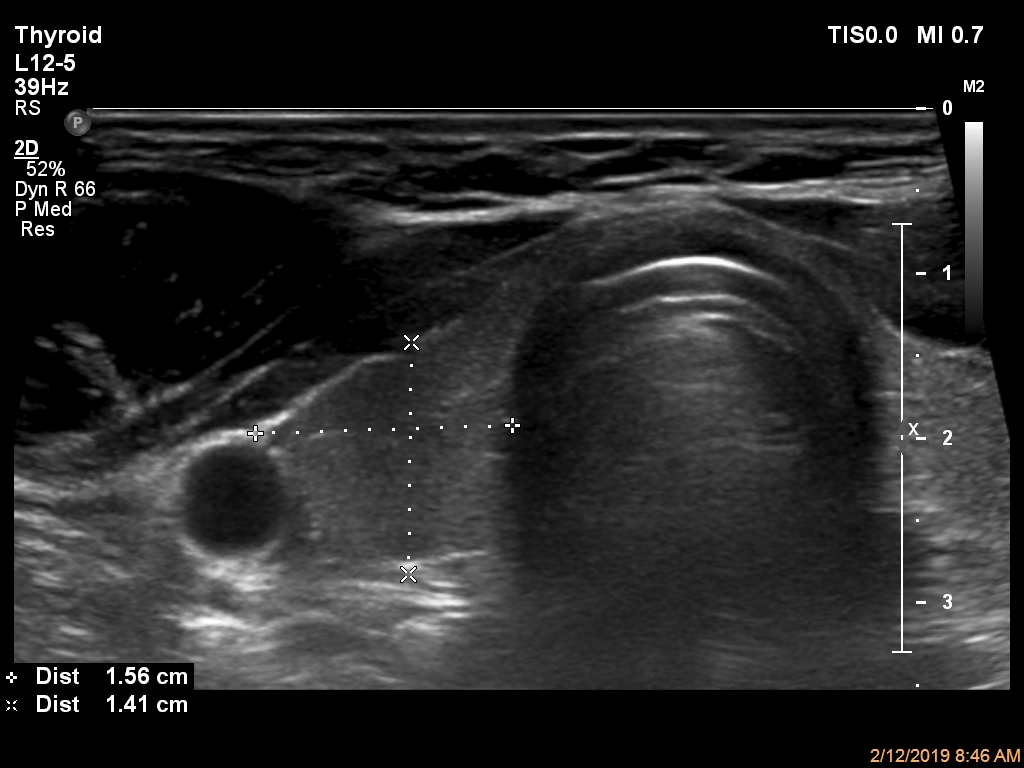

ابعاد و حجم تیروئید در سه قسمت لوب چپ (تصویر 1)، ایسم (تصویر 2) و لوب راست (تصویر 3) بررسی و معاینه میشود. همچنین سونوگرافی داپلر نیز در دو قسمت چپ (تصویر 4) و راست (تصویر 5) انجام میشود. لازم به ذکر است، همانطور که در قسمت آزمایشگاه توضیح داده شده است، هورمون TSH3 نیز به منظور غربالگری اختلالات کمکاری (کمتر از 0.01 µIU/mL) و پرکاری (بیشتر از 4 µIU/mL) انداز گیری و گزارش میشود. |